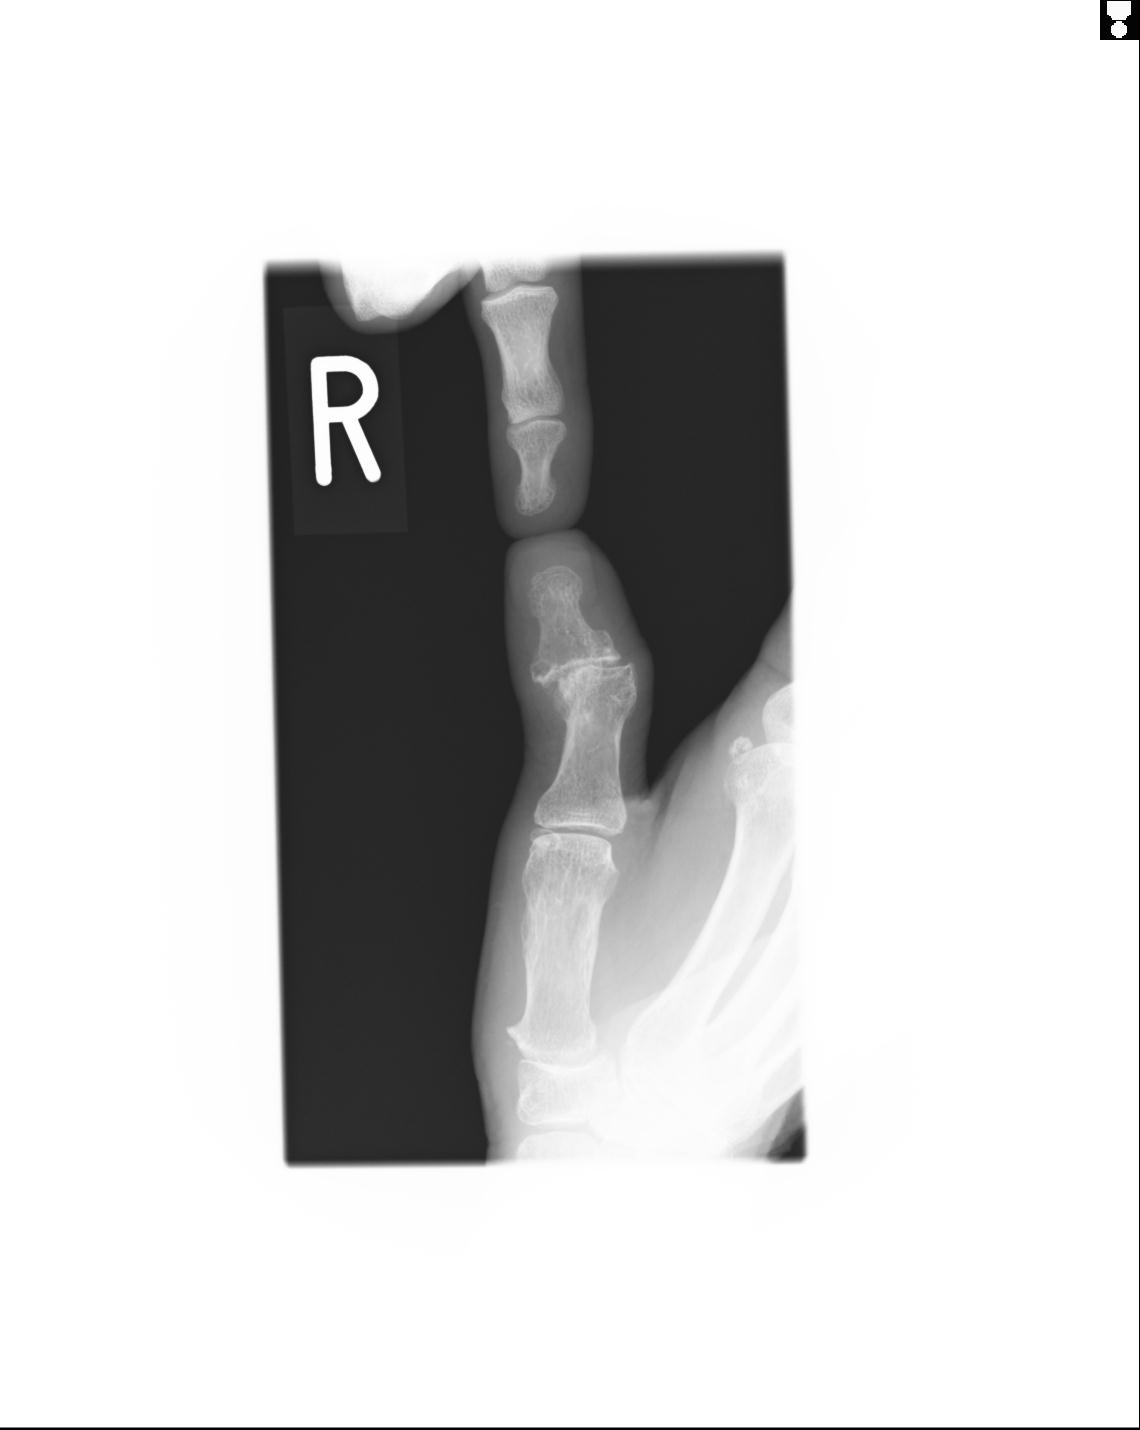

20857 1/11 左手 3R 1/19 4R 55歳男性 小指中節骨骨折